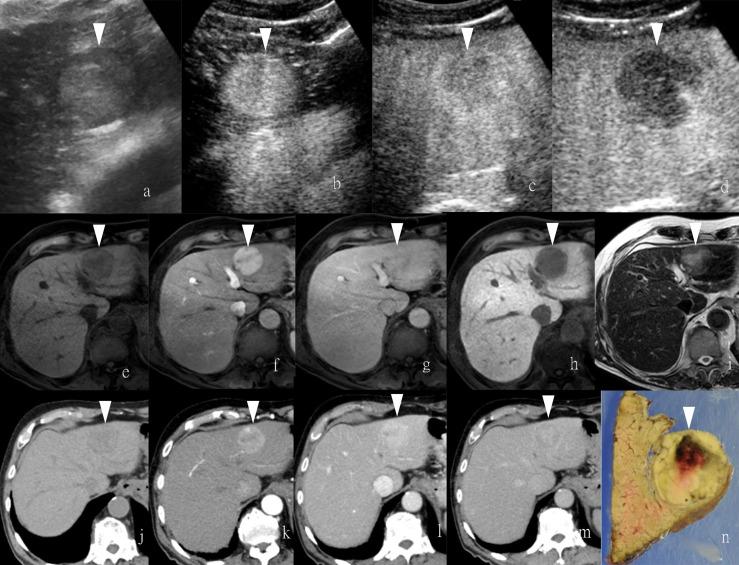

Contrast Agents for Hepatocellular Carcinoma Imaging: Value and Progression.

Hepatocellular carcinoma (HCC) has the third-highest incidence in cancers and has become one of the leading threats to cancer death. With the research on the etiological reasons for cirrhosis and HCC, early diagnosis has been placed great hope to form a favorable prognosis. Non-invasive medical imaging, including the associated contrast media (CM)-based enhancement scan, is taking charge of early diagnosis as mainstream. Meanwhile, it is notable that various CM with different advantages are playing an important role in the different imaging modalities, or even combined modalities. For both physicians and radiologists, it is necessary to know more about the proper imaging approach, along with the characteristic CM, for HCC diagnosis and treatment. Therefore, a summarized navigating map of CM commonly used in the clinic, along with ongoing work of agent research and potential seeded agents in the future, could be a needed practicable aid for HCC diagnosis and prognosis.